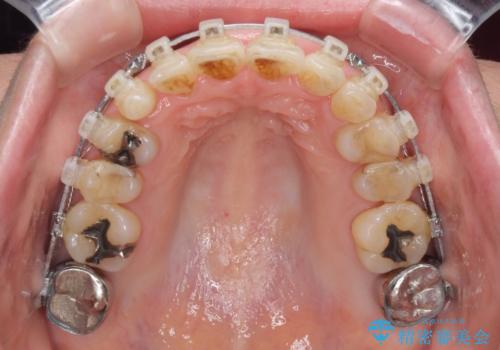

- 矯正装置

- クリアブラケット

近医での歯周病治療の影響でブラックトライアングルが発現していたため、IPR(歯と歯の間を削る)で隙間を改善しつつ、インプラントを固定源に歯列全体を後方へ移動させることとしました。